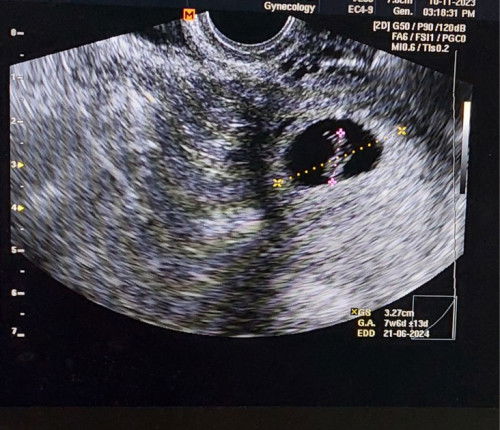

Hi mommies, sy dh byk kali buat scan since 5w pregnant tapi sampai skrg masih taknampak baby bila scan dekat perut. Semalam kandungan usia 9w5d scan dekat perut pun masih taknampak apa2. Siap Dr drip air supaya supaya pundi kencing penuh. Masih taknampak. Tapi masa kandungan usia 7w mcm tu Dr scan guna tvs scan sbb berapa kali dh scan kat perut xnmpk ape. Lepas scan tvs, Nampak je heartbeat. So semalam, scan kat perut usia 9w tknmpk apa. Mmg kena buat tvs scan eh baru nak nampak? Ada ke mommies usia kandungan 9w blm nampak masa scan? #ingintahu #firstmom #pleasehelp